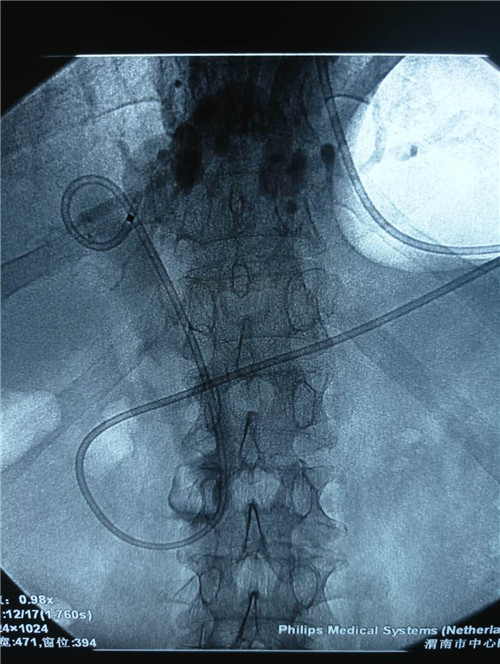

该患者男性,81岁,体温持续40摄氏度,血压80/50mmHg,心率120次/分,有结核病史,曾患脑梗死,右侧肢体活动障碍,精神极差,该手术风险极高,胆总管内多发大结石、急性化脓性胆管炎;这种状态下如果行开腹手术,死亡率极高。普外科史和平主任、王旭、吴云龙医生讨论后决定先行ERCP下鼻胆管引流术,首先缓解患者胆管炎症状,待患者症状减轻,生命体征平稳后再行下一步治疗。

然而对于如此高龄、如此重症的患者,行ERCP手术风险一样较大,但如果不做内镜下引流,患者只有死路一条。消化内镜中心与普外科的医护人员进行了充分讨论,制定了各种突发情况的应急预案,由曹鹏医生为患者行急诊ERCP手术。

曹鹏医生进十二指肠镜后看到肿大的乳头,利用切开刀+导丝超选进入胆管,行十二指肠乳头切开,随即大量脓性胆汁流出,并迅速留置鼻胆管。功夫不负有心人,终于,在主管护师许晓庆、护士王欣的配合下,又成功挽救了一名病患的生命,同时也彰显了市中心医院消化内镜中心医护人员极高的专业素养和娴熟的业务能力。